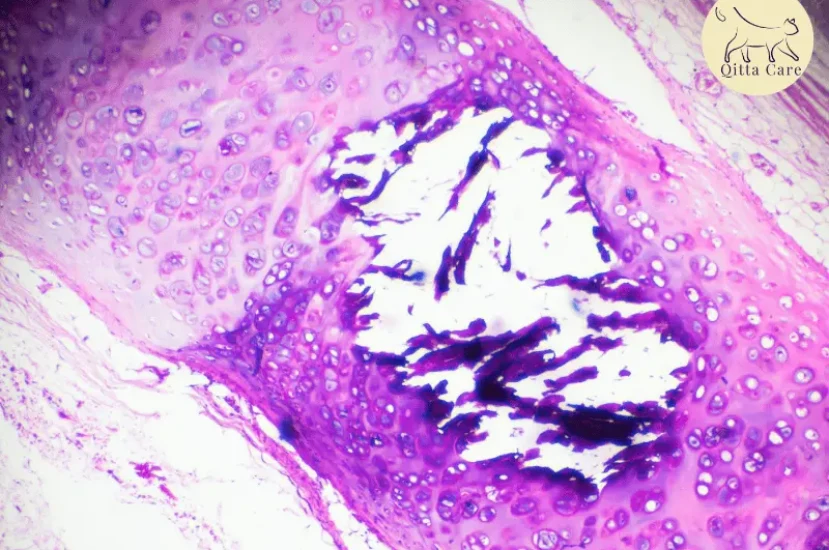

طرق تشخيص التهاب القصبات الهوائية المزمن عند القطط

يشمل التشخيص عدة خطوات:

- الفحص السريري: يتم استماع أصوات التنفس باستخدام سماعة الطبيب.

- الأشعة السينية (X-ray): تساعد في تحديد التغيرات في الرئتين والقصبات الهوائية.